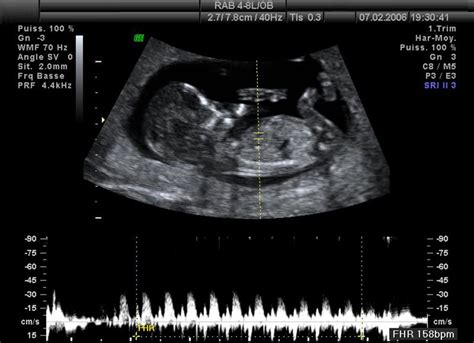

V tomto období dochádza k mimoriadne rýchlemu vývoju plodu. Základný vývoj srdiečka je už dokončený a má svoj charakteristický tvar. Vaše bábätko už má základy pečene, čriev, ľadvín, vyvíjajú sa pľúca a žalúdok. Tiež vnútorné pohlavné orgány, ktoré sa budú ďalej vyvíjať, aby neskôr mohli plniť svoju funkciu. Rýchlo sa vyvíja i mozog plôdiku. Rast hlavy sa spomaľuje a zrýchľuje sa rast telíčka. Plod vyzerá už ako takmer dokonalá zmenšenina človeka, stráca sa aj chvostík. Stále má však priesvitnú kožu, a nielen že je priesvitná, ale aj prepúšťa plodovú vodu. Očká sú stále zatvorené, ústa, v ktorých sa tvorí jazyk sa už otvárajú, tvoria sa i zubné lôžka. Vyvíjajú sa zárodky zmyslov. Malý plod prehĺta, dokonca i ciká. Na ultrazvuku ho lekári zachytia často v pohybe.

Prvé týždne tohto mesiaca však stále patria medzi rizikové. V tomto období plod začína reagovať na podráždenie pohybom a podľa niektorých štúdií už začína vnímať aj bolesť.